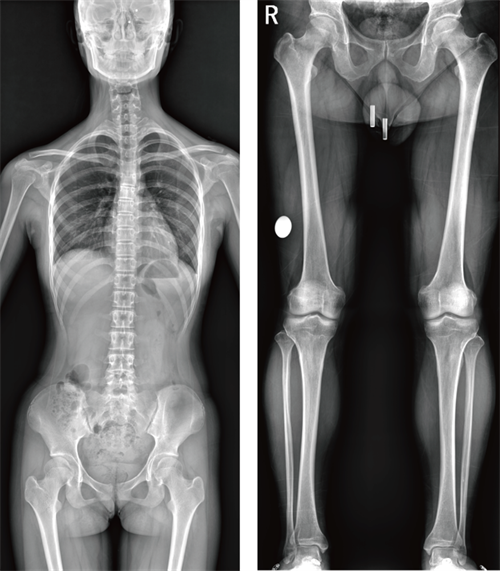

除了动态功能成像与断层融合技术,腾灵2在SLOT窄缝拼接技术上也实现了本质性的突破。传统的全身拼接往往需要三到四次曝光、分段拍摄后再由软件进行拼接,这个过程不仅操作繁琐,更重要的是存在拼接错位和图像比例失真的风险。而腾灵2采用的SLOT窄缝成像原理,通过球管与探测器的同步匀速移动,以狭缝式曝光一次性采集全下肢或全脊柱的图像数据,没有拼接痕迹,并且支持负重位下的检查。以全下肢摄影为例,只有在患者站立负重状态下拍摄的下肢全长片,才能真实反映膝关节内外翻畸形以及下肢力线的真实走向,这对于关节置换和矫形手术的术前规划具有不可替代的价值。

(新一代动态功能成像技术胃肠机腾灵2狭缝拼接图像展示)